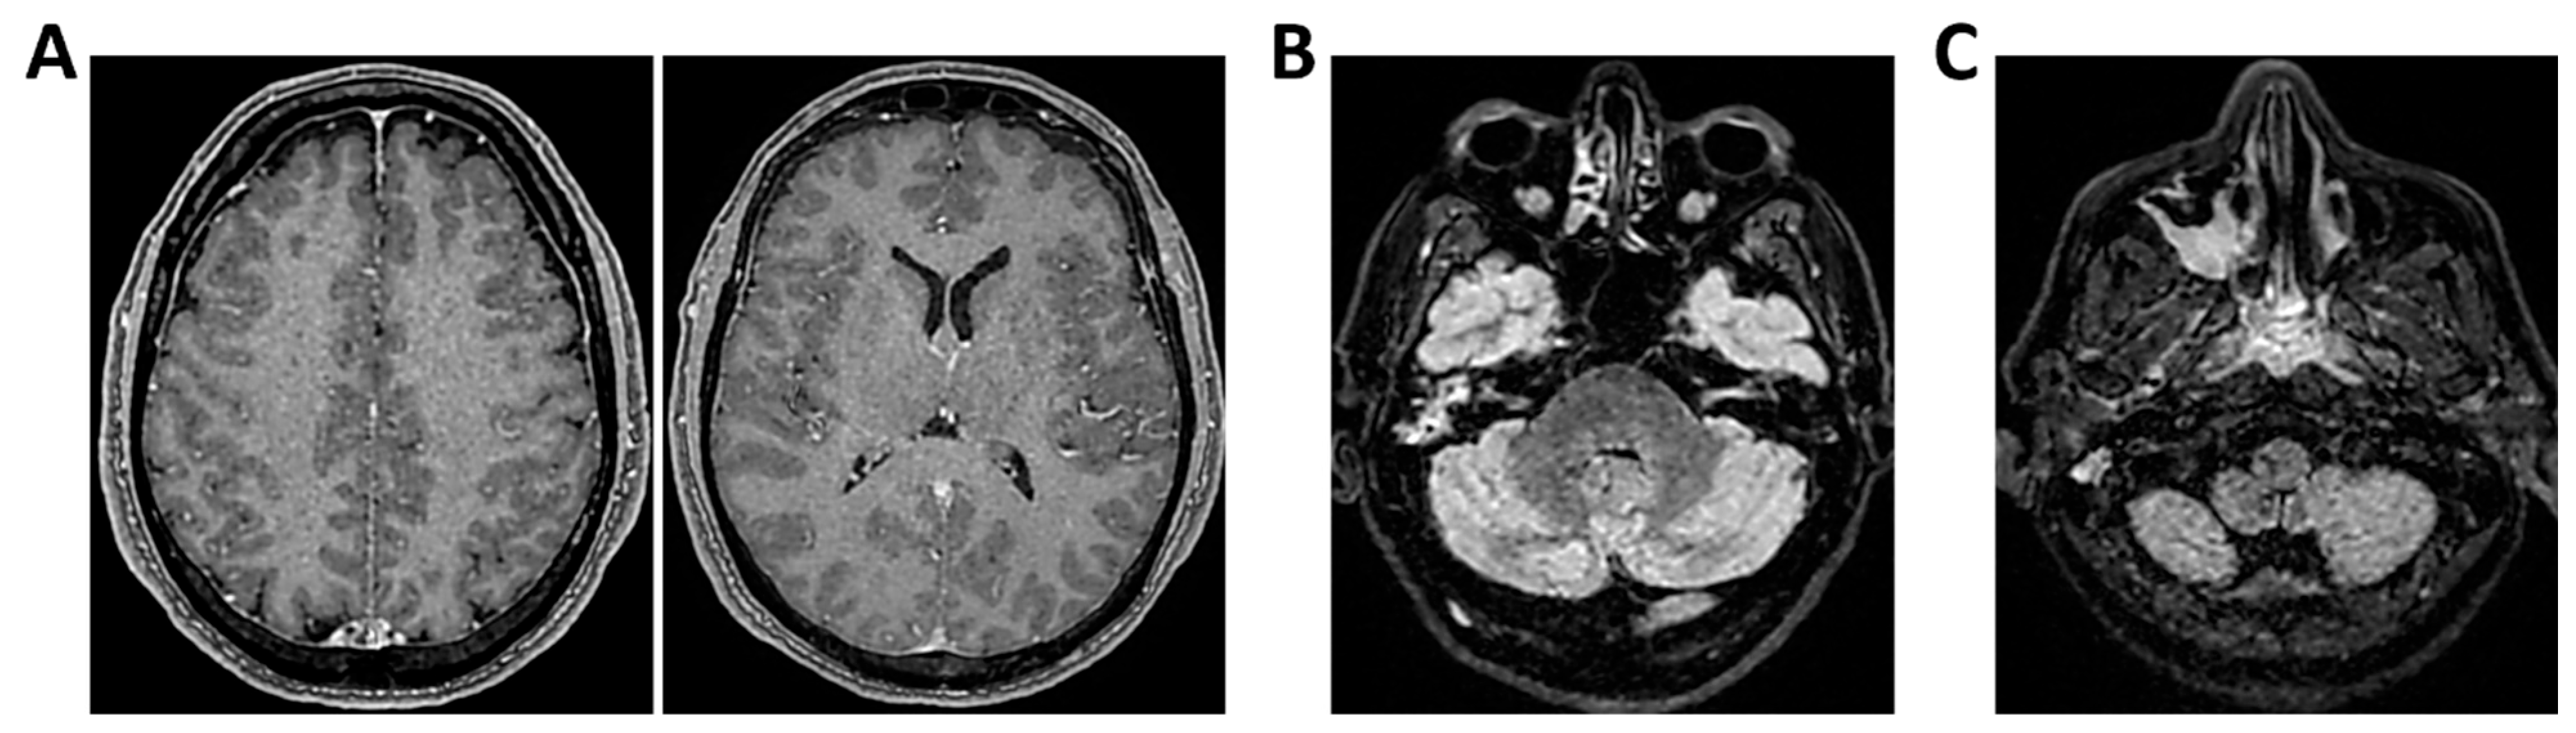

Figure 9.

MRI of patient 4 group 2. A 35-year-old HIV-positive man, diagnosed in 2018 with pneumocystosis (PCP) and non-compliant with Highly Active AntiRetroviral Therapy (Biktarvy), presented with bilateral otalgia, progressive hearing loss, left-sided hemiparesis, and impaired coordination. He was hospitalized and reinitiated Biktarvy and PCP prophylaxis with Bactrim. He received broad-spectrum antibiotics for bilateral otomastoiditis and ganciclovir for CMV viremia. Brain MRI revealed findings consistent with progressive multifocal leukoencephalopathy (PML). After discharge, worsening left hemiparesis and new-onset dysarthria led to readmission. A follow-up CT showed progression of subcortical white matter lesions. Lumbar puncture, urine, and plasma were all positive for JC virus. The patient was transferred to the ICU for further management. On day 2, TCCD showed PI of 1.50 on the right and 1.07 on the left, indicating mild asymmetry but no definitive signs of intracranial hypertension. (A) MRI exam shows large areas of altered signal intensity, without significant mass effect, hyperintense in 3D axial FLAIR sequence, (B) with peripherical diffusion restriction in axial DWI sequence, (C) without contrast enhancement in 3D axial T1 FSPGR, involving both cortical and deep regions of the frontal, temporal and parietal regions bilaterally, as well as right insular and thalamic regions. Additionally, the brainstem with left-sided predominance and the right middle cerebellar peduncle are involved. These alterations are consistent with PML. (D) MRI perfusion study documents minimal increase in CBF in the more cranial regions on the right. Blue circles indicate the ROI used for quantitative CBF analysis.

3.2. Group 2: TCCD and Perfusion MRI with ASL

The remaining two patients in this group experienced poor outcomes. One was diagnosed with progressive multifocal leukoencephalopathy (PML) due to JC virus and presented with a right-dominant perfusion asymmetry and elevated right-sided PI (1.50). MRI revealed extensive subcortical and infratentorial lesions, including the brainstem (Table 3 and Figure 9).